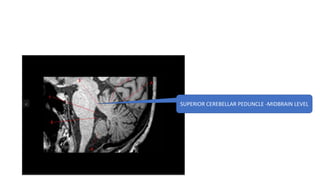

SUPERI0R CEREBELLAR PEDUNCLE -MIDBRAIN LEVEL

SUPERIOR CEREBELLAR PEDUNCLE -MIDBRAIN LEVEL

MIDDLE CEREBELLAR PEDUNCLE AT PONS